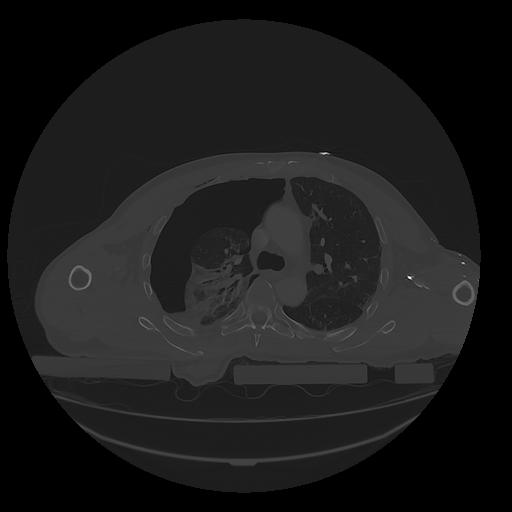

31 PULMON,CE,Vol,1.0,PULMON,,